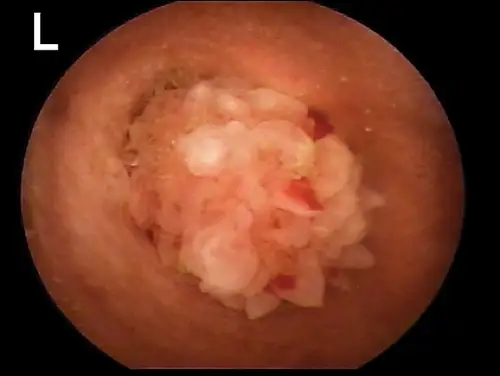

Any change in the epidermis, such as with ceruminous gland hyperplasia or ulceration, is significant and should be noted (Figure 4). In a patient with inflammatory ear disease, thickening of the epithelium may obscure visualization of blood vessels. The clinician should assess for presence of stenosis. Some dog breeds (eg, shar-peis, pugs) have small-diameter ear canals as part of their standard conformation. Differentiation between swelling and stenosis is necessary. Stenosis results from permanent pathologic changes within the epidermis of the ear canal (Figure 5).

selected slide image

FIGURE 4

1 / 2

Cerumen gland hyperplasia. Inflammation in the ear canal results in increased secretions from the apocrine glands, which enlarge above the epithelial surface.

For swelling of the ear canal caused by inflammation, it may be necessary to delay a complete examination of the ear canal until anti-inflammatory therapy (eg, systemic or topical corticosteroids) decreases the swelling.

If changes do not reverse, the prognosis for medical management is poor, and total ear canal ablation and/or bulla osteotomy is recommended. If the ear canal epithelium is smooth and pink in color but the ear canal diameter is narrowed, hyperplasia of the sebaceous glands may be present.